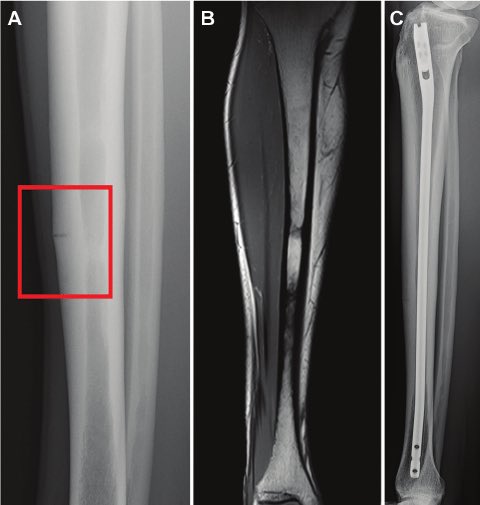

🔅طيب كيف نشخص هذه الكسور ؟!

يمكن للأطباء احيانا التشخيص من خلال الفحص البدني و التاريخ الطبي ولكن غالبًا ما تكون هناك حاجة لإجراء عمل الأشعة .

والتشخيص يتم عن طريق اشعة MRI وهي الاكثر دقة لتشخيص هذا النوع من الكسور على عكس الأشعة العادية X-Ray